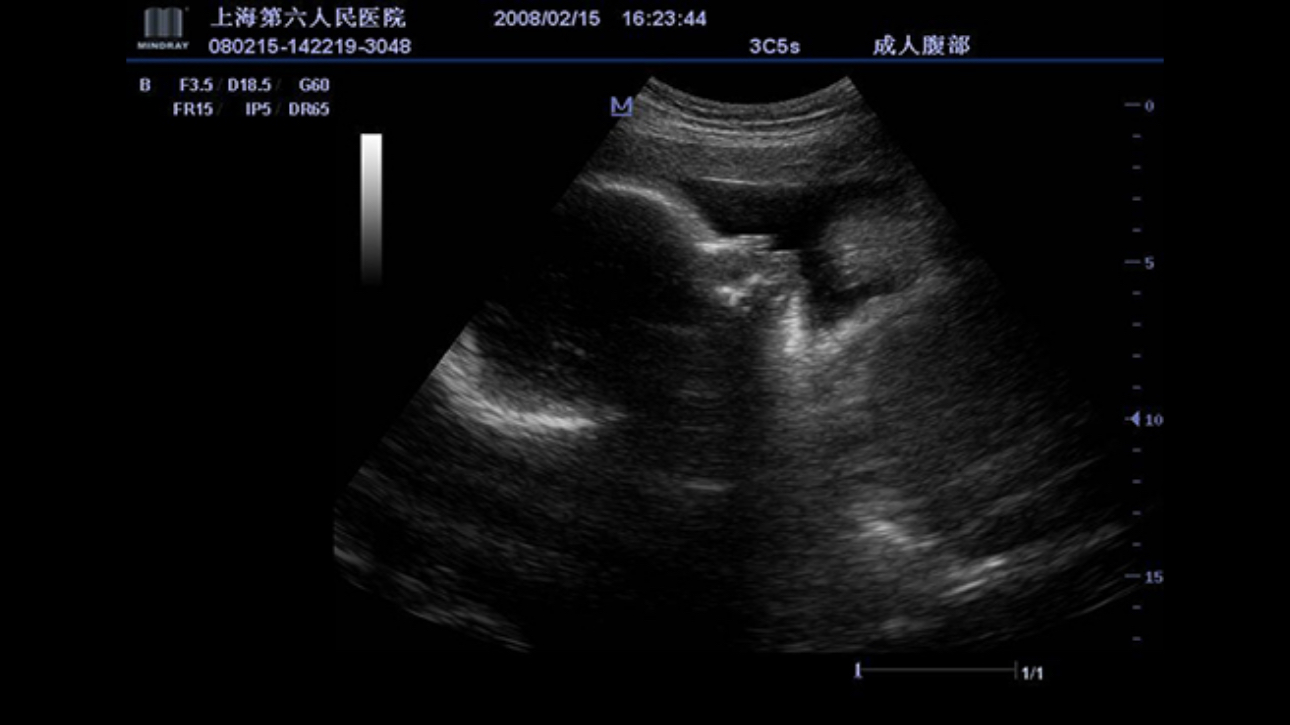

A fully-featured laptop style color Doppler system, M5 offers uncompromised 2D performance and exceptional value in a highly convenient and easy to use package. Equipped with advanced technologies such as Smart 3D TM and efficient workflow software, makes M5 ideal for use within obstetrics and gynecology application field.

Performance

PSHITM(Phase Shift Harmonic Imaging)

Purified Harmonic Imaging for better contrast resolution providing clearer images with excellent resolution and less noise.

Permits use of multiple scanned angles to form a single image, resulting in enhanced contrast resolution and improved visualization.

iClearTM(Speckle Suppression Imaging)

Gain improved image quality based on auto structure detection